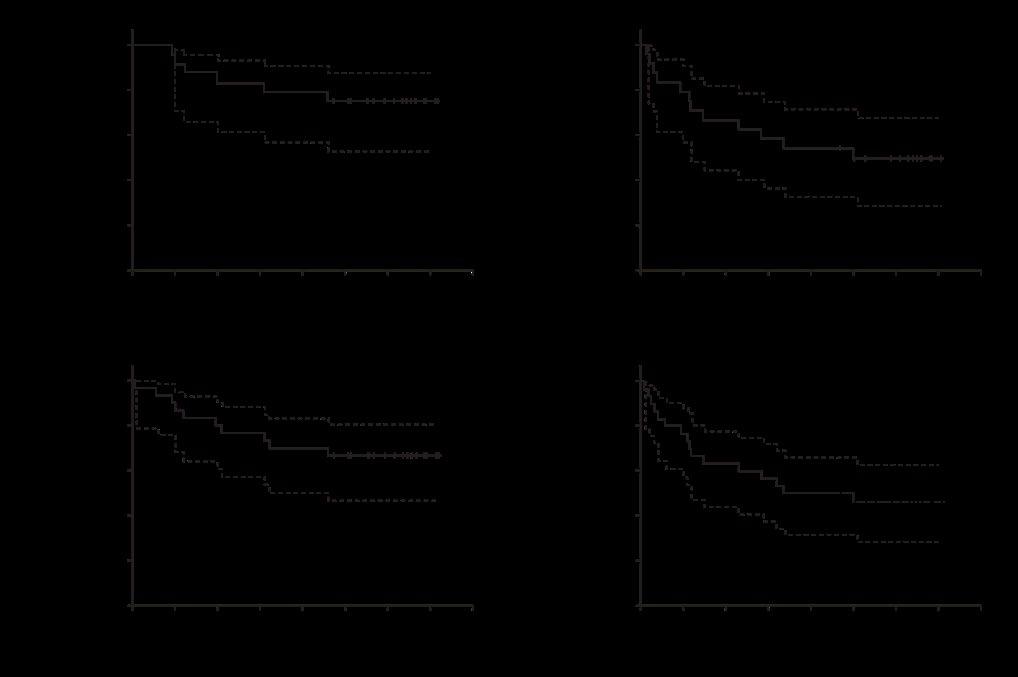

Results showed that, at the time of data cutoff on 26th September 2023, 265 patients received Isa-VRd, and 181 received VRd. The median treatment duration was 53.2 months for Isa-VRd compared to 31.3 months for VRd. At a median follow-up of 59.7 months, median PFS was not reached for Isa-VRd vs 54.3 months for VRd. The hazard ratio (HR) for PFS was 0.596 (98.5% CI: 0.406–0.876), indicating a significant reduction in the risk of progression or death by 40.4% with Isa-VRd. The PFS benefit was consistent across subgroups and maintained through subsequent lines of therapy and the addition of Isa did not significantly affect the relative dose intensity of VRd.

The study results demonstrate that Isa-VRd significantly reduces the risk of disease progression or death by 40.4%, compared to VRd alone, while providing deep and sustained responses. Additionally, the safety profile of Isa-VRd was consistent with the addition of Isa, and the observed numerical differences in treatment-emergent adverse events were largely due to longer exposure in the Isa-VRd arm. These results support Isa-VRd as a potential new standard of care for transplant-ineligible patients with NDMM.

In the APOLLO Trial, an open-label, prospective, multicentre multinational Phase III trial, patients were randomised 1:1 to receive ATRA-ATO plus two shots of idarubicin, or ATRA-CHT. The study found that the 2-year survival rate in the ATRA-ATO group (88%; 95% CI: 80–96%) was

significantly higher than in the ATRACHT group (70%; 95% CI: 59–83%; P=0.02). The main factors explaining the improved event-free survival were incidence of molecular relapse and molecular resistance.

The authors concluded that first-line therapy with ATRA-ATO with two initial doses of IDA results in superior eventfree survival compared to conventional ATRA-CHT in patients with HR-APL, which may support implementation of this regimen as the new standard of care for patients with HR-APL.

At the primary analysis cut-off date of 29th March 2023, Glofit-GemOx demonstrated a significant OS benefit with a hazard ratio of 0.59. With a median followup of 11.3 months, the median OS for the Glofit-GemOx group was not reached, while

it was 9 months for the Rituximab-GemOx group. The Glofit-GemOx group also showed a marked improvement in PFS with a hazard ratio of 0.37 and a significantly higher complete remission rate (50.3%) compared to the Rituximab-GemOx group (22.0%).

At the primary analysis cut-off date of 29th March 2023, Glofit-GemOx demonstrated a significant OS benefit with a hazard ratio of 0.59

A follow-up analysis with a median follow-up of 20.7 months reinforced these findings, showing continued superiority of Glofit-GemOx in median OS (25.5 versus 12.9 months) and PFS (13.8 versus 3.6 months). Adverse event rates were higher in the Glofit-GemOx group, including serious adverse events such as cytokine release syndrome. However, when adjusted for exposure differences, the rates were comparable between the groups.

The study authors concluded that Glofit-GemOx offers a statistically significant and clinically meaningful improvement in survival outcomes for patients with relapsed/ refractory DLBCL who are ineligible for autologous stem cell transplant.